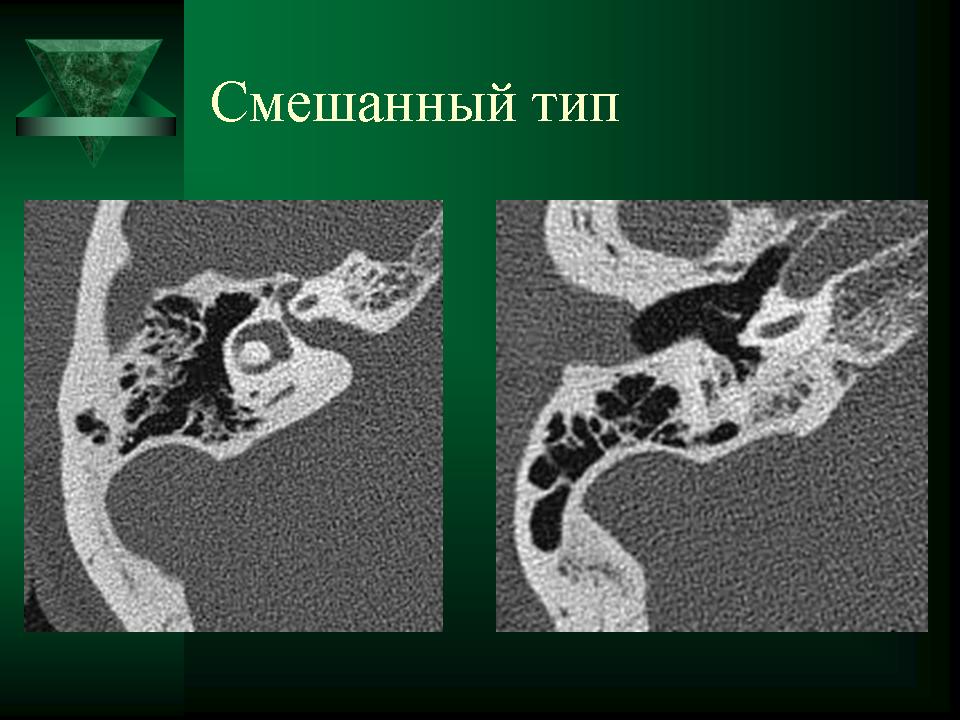

КТ анатомия сосцевидного отростка: особенности и показания